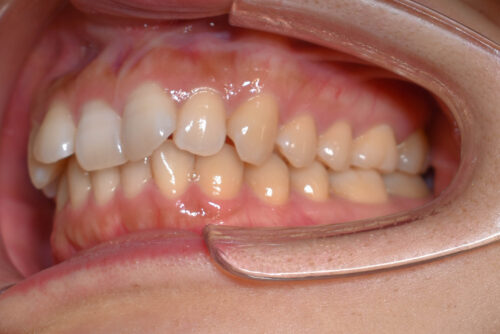

右側が アングル2級とよばれる

出っ歯傾向の状態で

上の正中が

半歯分 ずれている状態でした。